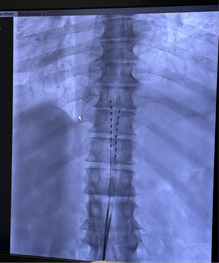

from clipboard

患者术前MRI